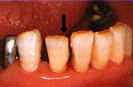

図5.仮封後1週間経過。知覚過敏、

脱落等の不快症状は認められない